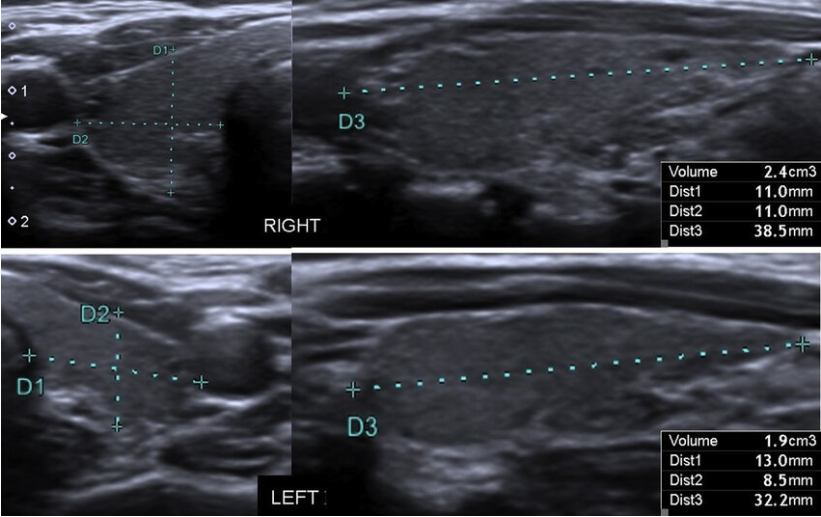

Ellipsoid Method: Volume of one lobe = 0.523 × Width × Depth × Length

*Width : Left-right width of thyroid lobe (Transverse plane)

*Depth : Anterior-posterior thickness[A-P] of thyroid lobe (Transverse or Longitudinal plane)

*Length : Longitudinal length of thyroid lobe (Longitudinal plane)

※ Normal adult thyroid volume: approximately 15 ~ 20mL